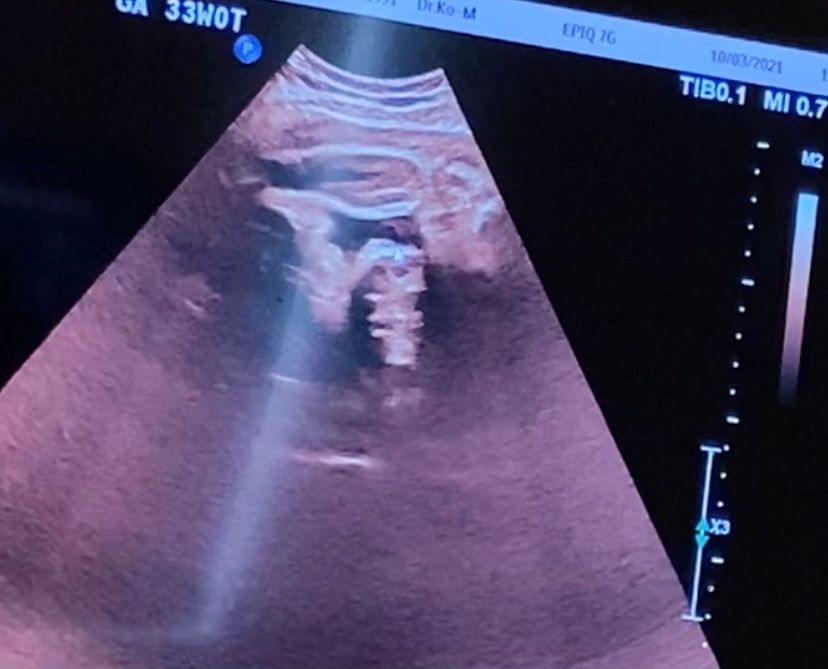

33 недели, кто рожал девочку а оказалось мальчика😅

УЗИ, КТГ, доплерСегодня был осмотр,узи ,ктг. Все супер, высокая(,вроде девочка)47 см. Вес средний -2230. Шейка почти 50 мм 😰я думала уже покороче.

а вот пол , у моего врача с самого начала под вопросом, вроде и девочка ,но она почему то не уверена. Постоянно сжатые ноги. Мне конечно уже все равно, я уже и хочу девочку и готово все для неё ,но вот эта неуверенность немного мучает. Вот только такие фото,но ничего здесь не видно, да?

Не могу понять, как вы на этих фотографиях вообще разбираете, где там пирожок, где ноги, где человек???